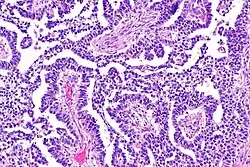

The ovarian yolk sac tumors, also known as endodermal sinus tumors, are accountable for approximately 15.5% of all OGCTs.[8] They have been observed in women particularly in their early ages, and rarely after 40 years of age.[9] The critical pathologic features are a smooth external surface and capsular tears due to their rapid rate of growth. A study consisting of 71 individual cases of ovarian yolk sac tumor provides evidence to the proliferation of the tumor. In one of the cases, the pelvic examination revealed normal activity until a 9 cm and 12 cm sized tumor was discovered 4 weeks later.[9] In another case, a 23 cm tumor was discovered in a pregnant woman who was monitored regularly and had normal findings until oophorectomy became essential.[9] Histologically, these tumors are characterized by mixed solid and cystic components.[1] The mixed solid components are characterized by a soft gray to yellow solid components accompanied with significant hemorrhage and necrosis. The cysts are approximately 2 cm in diameter and populated throughout the tissue which results in giving the neoplasm a 'honeycombed appearance'.[1]